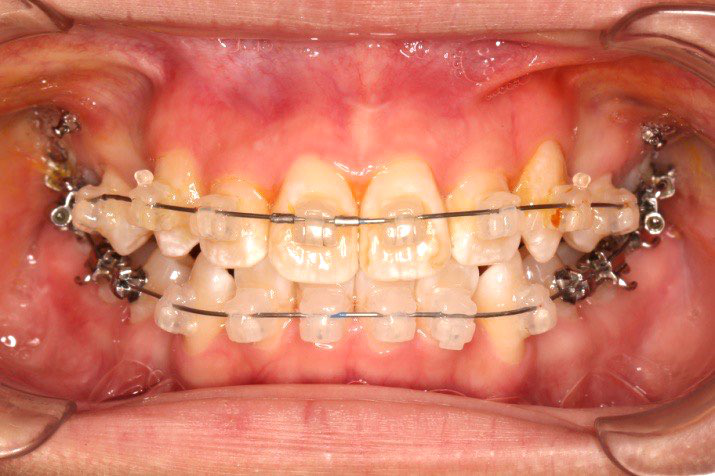

2018.11.14  术后侧面改善明显,露龈笑改善明显,笑弧笑线协调,颏部肌肉紧张度明显改善

2018.11.14  术后磨牙尖牙I类关系,中线齐,覆合,覆盖正常

Post-TXPRE-TXPost-TXNormFMIA°47°57.555.0SNA°77.7°76.883.0SNB°70.2°73.780.0ANB°7.5°3.13.0FMA° 29.828.026PFH/AFH70.5°65.970Z Angle°50.3°64.477U1-FH113.0103.7110.0 IMPA°103.291.197.0U Lip tos’ line6.3 mm3.25.0L Lip to s’ line3.9 mm1.03.0OP-FH1212.615

宏观评价:面部对称,面下三分一比例协调,上下唇凸度正常,上颌牙列内收转矩控制良好,下颌后缩改善,颏唇沟变得更加柔和,术后达到基本直面型。

迷你观评价:上下牙齿中线与面中线对齐,笑弧协调,微笑时牙龈暴露量正常,微笑时横向正常,左右唇基本对称。

微观评价:牙齿整齐,咬合关系良好,上下前牙转矩及突度控制良好,磨牙关系I类,尖窝咬合关系良好,OB,OJ正常。